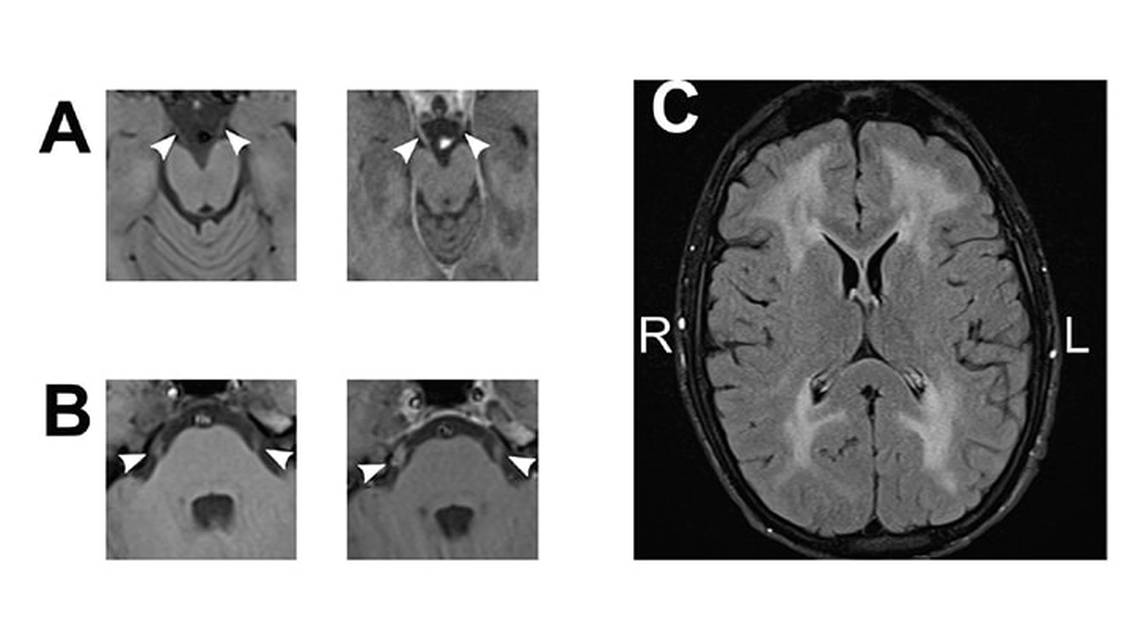

An extensive workup for inflammatory, metabolic, and heritable disorders was ordered. No metabolic or nutritional deficiencies were found. Erythrocyte sedimentation rate (ESR) and C-reactive protein (CRP) levels were mildly elevated, but serologic autoimmune markers were otherwise negative. EMG and nerve conduction studies (NCS) showed severe sensorimotor neuropathy with demyelinating and axonal features. Brain MRI, ordered to further investigate extraocular impairment, showed symmetric nonenhancing white matter changes with thickening and enhancement of multiple cranial nerves (Figure 1). Lumbar puncture was performed and cerebrospinal fluid (CSF) analysis was notable only for highly elevated protein. Follow-up was planned while lysosomal, peroxisomal, and genetic testing was pending. Muscle biopsy was not pursued.

Leukoencephalopathy was present in all cases that had imaging available. Although the majority of individuals were considered minimally symptomatic from this manifestation, 20% experienced significant cognitive impairment. The leukoencephalopathy of MNGIE is characterized by progressive and extensive involvement of the subcortical white matter with sparing of the U-fibers.6 There is variable involvement of the deep gray structures and brainstem. Cranial nerve thickening as seen in Mr. E has been noted in only 1 other case,7 although this subtle finding may be frequently overlooked.